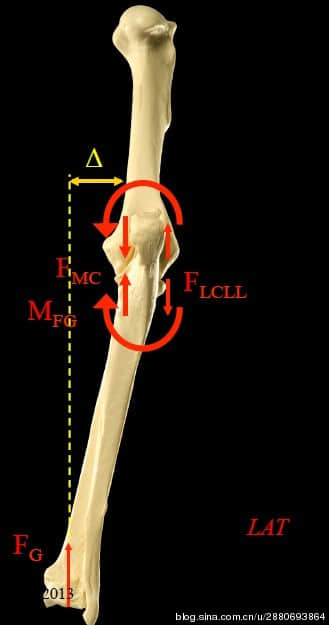

我们认为其中一个很重要的肘关节发育不良的原因是桡尺骨发育不平衡(通常是尺骨短了)引起肘关节不平衡。

上图是一个动物的右手,从背后看,左边是动物的内侧,右边是动物的外侧。我们可以看到这个动物坐姿像一个淑女(第一张图右边的一条狗),把手收到身体之内。我们可以看到这个动物的肘关节是内侧受力比较严重,外侧是一个拉开的力量。所以这个关节受力都集中在内侧(图的左侧)。最终,这只手就会因为内侧受到磨损导致肘关节发育不良综合症,于是就会疼痛跛行,继而增生,严重的会引起骨头的分离和断裂。

由于肘关节受力问题引起了一系列的症状和疾病,所以在诊断上也需要看肘关节受力的情况。一般传统拍摄x光片的方法是让狗狗的手在一定角度下去拍摄x光片,以观察狗狗肘关节的病变。但是这种方式不能反映出狗狗肘关节的受力情况。于是,我们SAO讲师团队,参考了最新的研究成果,开发并定制了一套使肱骨和桡骨在同一直线水平面上,让前肢受力的情况下拍摄x光片的专用保定工具。用保定工具或者特殊保定方法拍摄出来的x光片更能反应出肘关节的受力情况,为宠物医师临床上提供更好的依据。我们也可以根据肘关节肱骨内外髁与桡尺骨中垂线的受力情况测量出受力角度(正常犬在81.5度左右)。通过分析受力的情况,从而制定治疗方案。